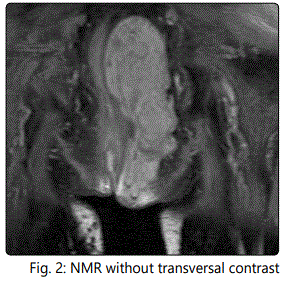

56-year-old man seen in consultation because of an injury on the left gluteus that causes discomfort. Magnetic resonance imaging of non-contrasting pelvis is performed for the diagnosis, which describes a large tumor with dimensions of 16 x 7 x 6 cm with well defined contours, lobed, located at the level of the ischiorectal fossa, displacing the elevator ani muscle and extending caudally towards the subcutaneous cellular tissue of the left gluteal region, without involvement of prostate, seminal vesicles and bladder. PAAF is guided by ultrasound and the pathological study shows fibroadipose tissue with vascular ectasia.

In our case the patient presents the tumor in perianal location. After the radiological study and biopsy, surgical treatment by means of a complete resection of Ligasure Impact tumor was chosen, observing a large tumor to the upper edge of the prostate. The preoperative anatomopathological results of fibroadiposal tissue with vascular ectasia differ from those analyzed by the surgical specimen resulting in atypical sclerosing lipomatous lesion with MDM2 expression in histology. This low-grade tumor is currently classified as a well-differentiated liposarcoma with poor metastasis and relapse after RO excision. The surgical treatment carried out does not manage to obtain free margins. After the patient's agreement with the treatment, he stated that he did not want to undergo surgical techniques, so no other resection was performed to expand the margins. Long-term observation of the patient is decided. After 12 months of follow-up he has not shown recurrence of the disease at present.